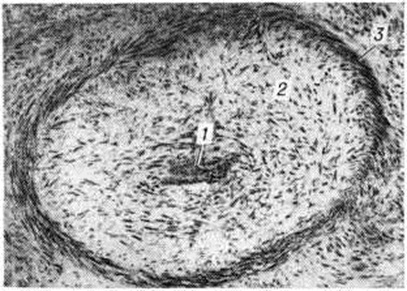

При гнойном Менингит воспалительный выпот имеет сначала серозный характер, а на 2—3-й день заболевания он приобретает вид гнойного экссудата. При этом мягкие оболочки полушарий мозга (цветной рисунок 1), сосудистые сплетения и эпендима пропитаны мутной желтовато-зеленоватой вязкой ЖИДКОСТЬЮ. При обильном накоплении гнойнофибринозный экссудат образует «чепчик» в лобной и теменной долях полушарий (цветной таблица, ст. 33, рисунок 2) или окутывает весь мозг сплошной массой. Он заполняет также мозговые полости, покрывая желтоватой плёнкой сплетения и стенки желудочков. Развивающаяся обтурация ликворных путей выпотом ведёт к острому расширению желудочков мозга (цветной рисунок 3) и церебральной гипертензии. В воспалительный процесс могут вовлекаться подоболочечные отделы мозгового вещества, но особенно часто области, окружающие желудочки. При своевременно начатом лечении гнойный экссудат подвергается ферментативному распаду и резорбции, но в некоторых случаях он организуется, вызывая спаечный процесс в оболочках и желудочках мозга. Развивается хронический гнойный или хронический продуктивный (адгезивный) лептоменингит, характеризующийся частичной облитерацией подпаутинного пространства с образованием между листками мягкой оболочки замкнутых гнойных или серозных полостей. Спайки могут рассекать также и желудочки мозга, формируя отдельные заполненные гноем или цереброспинальной жидкостью камеры. Макроскопическую картину хронический продуктивного Менингит дополняет склероз оболочек, сплетений и эпендимы с полной или частичной облитерацией находящихся здесь сосудов. Резко нарушаются циркуляция цереброспинальной жидкости и мозговая гемодинамика, что ведёт к развитию гидроцефалии. Гистологически в оболочках, эпендиме и сплетениях обнаруживается картина хронический гнойного воспаления с выраженными склеротическими изменениями. В соседних участках мозговой ткани можно наблюдать поля клеточного опустошения с дистрофией и гибелью нейронов и накоплением в них липофусцина, демиелинизацию нервных волокон и очаговый глиоз. Описанные изменения могут выявляться и без предшествующей клиники острого Менингит, через несколько лет после травмы, инфекционного заболевания или оперативного вмешательства. Если в оболочечном выпоте содержатся эритроциты и, следовательно, мягкие мозговые оболочки окрашиваются в различные оттенки красного цвета, то такое воспаление этих оболочек носит название геморрагического (цветной рисунок 2). Геморрагический лептоменингит (цветной рисунок 4) может осложнить инфекционные заболевание, сопровождающееся общим тромбогеморрагическим синдромом или местной гиперергической реакцией немедленного типа. Сходную макроскопическую картину из-за примеси крови имеет реактивное воспаление в зоне субарахноидального кровоизлияния. Дифференциальной диагностике в этих случаях может помочь гистологический исследование материала — при инфекционном геморрагическом Менингит обнаруживают фибриноидные некрозы сосудов (смотри полный свод знаний Фибриноидное превращение), их тромбоз и преимущественно гранулоцитарную инфильтрацию очага воспаления. Туберкулёзный лептоменингит — результат гематогенной генерализации или лимфогенного распространения инфекции из лёгочного, лимфожелезистого (или другого внелёгочного) очага. Современные методы лечения изменили морфологический картину заболевания. На смену острому серозно-фибринозному воспалению оболочек мозга, дававшему раньше почти 100% летальность, пришли хронический ограниченные формы поражения со значительно лучшим прогнозом. При остром туберкулёзном Менингит желатинозный серовато-желтоватый выпот обнаруживается в подпаутинном пространстве головного (цветной рисунок 5) и спинного мозга в типичных местах, а также в полостях мозга. В мягкой оболочке и в эпендиме заметны милиарные или более крупные сероватые бугорки (цветной рисунок 6). Пропитанная серозно-фибринозным выпотом ткань может подвергаться казеозному некрозу (цветной рисунок 7). Микроскопически в инфильтрате с первых же дней заболевания преобладают лимфоциты. Самой характерной гистологический чертой подострых и хронический форм туберкулёзного воспаления является образование преимущественно эпителиоидно-клеточных гранулем (цветной рисунок 5), нередко с казеозным некрозом их центра. Подобные гранулемы обнаруживаются и в стенке сосудов, в которых можно видеть также и другие изменения — от серозного пропитывания до фибриноидного и казеозного некроза с тромбозом и развитием инфарктов головного мозга. При туберкулёзном Менингит в воспалительный процесс часто вовлекаются смежные отделы мозговой ткани, в которой развивается картина казеозного (цветной рисунок 6) или гранулематозного (рисунок 2) энцефалита. В исходе туберкулёзного воспаления в субарахноидальном (и даже субдуральной) пространстве головного и спинного мозга могут возникать спайки. Просвет проходящих здесь сосудов облитерируется (рисунок 3 и 4), что приводит к тяжёлым нарушениям циркуляции цереброспинальной жидкости и к расстройству гемодинамики. При амёбном Менингит (менингоэнцефалите), вызываемом неглериями, патолого-анатомически выявляется гнойный лептоменингит, геморрагический некротизирующий менингоэнцефалит, отёк мозга, периваскулярные скопления амёб. Морфологически картина при менингоэнцефалите акантамебного происхождения проявляется гранулематозным энцефалитом с очаговыми некрозами. Клиническая картинаМенингеальный синдром и изменения цереброспинальной жидкостиДля всех форм Менингит характерно наличие симптомов, объединяемых в менингеальный, или оболочечный, синдром. Полный менингеальный симптомокомплекс наблюдается не всегда даже при гнойном Менингит Нередко, особенно у детей раннего возраста, лиц старческого возраста, выявляется лишь часть менингеальных симптомов. К менингеальному синдрому относятся головная боль, рвота, общая гиперестезия, специфическая менингеальная поза, ригидность затылочных мышц, симптомы Кернига, Брудзинского, симптом подвешивания Лесажа, скуловой симптом Бехтерева н другие Головная боль — постоянный симптом, наблюдается практически у всех больных при различных формах Менингит Она может быть диффузной или локализованной (преимущественно в области лба и затылка). Возникновение головной боли связано с раздражением чувствительных окончаний тройничного нерва, а также парасимпатических (блуждающий нерв) и симпатических волокон, иннервирующих оболочки головного мозга. Рвота обычно сопровождает головную боль, возникает без связи с приёмом пищи, имеет «фонтановидный» характер. Рвота при Менингит— центрального происхождения и связана с раздражением рецепторов блуждающего нерва пли его ядер, расположенных на дне IV желудочка, или рвотного центра в ретикулярной формации продолговатого мозга. Важным симптомом является общая кожная гиперестезия и повышенная чувствительность к звуковым и световым раздражителям (гиперакузия, светобоязнь). Выявление этого симптома в раннем детском возрасте затруднено, так как дети обычно негативно относятся к осмотру, раздражаются при прикосновении к ним, капризничают, отворачиваются при ярком свете. В основе общей гиперестезии лежит раздражение задних корешков, а возможно и клеток спинномозговых узлов. Характерна поза больного: запрокинутая голова, выгнутое туловище, «ладьевидный» втянутый живот, руки прижаты к груди, ноги подтянуты к животу (менингеальная поза, поза «лягавой собаки», «взведённого курка»). Менингеальная поза — следствие рефлекторного тонического сокращения мышц. Запрокинутая голова больного обусловлена ригидностью затылочных мышц — повышением тонуса мышц-разгибателей шеи. При попытке наклонить вперёд голову больного, находящегося в положении лёжа, выявляется напряжение мышц затылка, при этом подбородок больного привести к грудной клетке не удаётся. Любая попытка вывести голову больного из её фиксированного положения сопровождается резкой болезненностью. Симптом Кернига (смотри полный свод знаний Кернига симптом) — очень ранний и характерный симптом поражения мозговых оболочек. Он выражается в невозможности разогнуть в коленном суставе ногу, предварительно согнутую под прямым углом в коленном и тазобедренном суставах (рисунок 5). Следует отличать симптом Кернига от анталгического (мышечного) сопротивления при симптоме Ласега (смотри полный свод знаний Радикулит). У детей раннего возраста симптом Кернига может не выявляться. У новорожденных и детей первых двух месяцев жизни, а также у больных паркинсонизмом, миотонией симптом Кернига может быть следствием физиологический или патологический повышения общего тонуса мышц. Верхний симптом Брудзинского выражается в непроизвольном сгибании ног в коленных суставах в ответ на попытку привести голову к груди в положении лёжа на спине (рисунок 6). Скуловой симптом Брудзинского — та же реакция при перкуссии скуловой дуги. Лобковый симптом Брудзинского выражается в сгибании ног в коленных суставах при надавливании на лонное сочленение. Нижний симптом Брудзинского исследуется одновременно с симптомом Кернига: при попытке разогнуть ногу в коленном суставе вторая нога сгибается в колене и приводится к животу. Симптом Гийена аналогичен нижнему симптому Брудзинского — при сдавливании четырех-главой мышцы одной ноги другая нога сгибается в колене и приводится к животу. Напряжение длинных мышц спины является также частым и типичным признаком менингеального синдрома и выявляется в виде следующих симптомов. Симптом Мейтуса: больному, лежащему на спине, фиксируют разогнутые в коленях ноги правой рукой, а левой рукой поддерживают спину, помогая ему сесть. При менингеальном синдроме спина больного и разогнутые ноги в положении сидя образуют тупой угол: больной не может сидеть прямо при разогнутых ногах. Симптом Фанкони — невозможность самостоятельно сесть в постели при разогнутых и фиксированных коленях. Симптом «треножника» — больной может сидеть в кровати, лишь опираясь руками позади спины. Симптом «поцелуя колена» — больной не в состоянии даже при согнутых в тазобедренных суставах нижних конечностях прикоснуться губами к колену. Довольно постоянным у больных всех возрастов является скуловой симптом Бехтерева: при перкуссии скуловой дуги усиливается головная боль и непроизвольно возникает болезненная гримаса на соответствующей половине лица. У детей раннего возраста определяется симптом подвешивания Лeсажа: поднятый под мышки ребёнок подтягивает ноги к животу и сохраняет их в этом положении, при этом голова слегка запрокинута назад (здоровый ребёнок при этой пробе свободно сгибает и разгибает ноги). Большое диагностическое значение у детей раннего возраста имеет симптом Флатау — расширение зрачков при быстром наклоне головы вперёд.